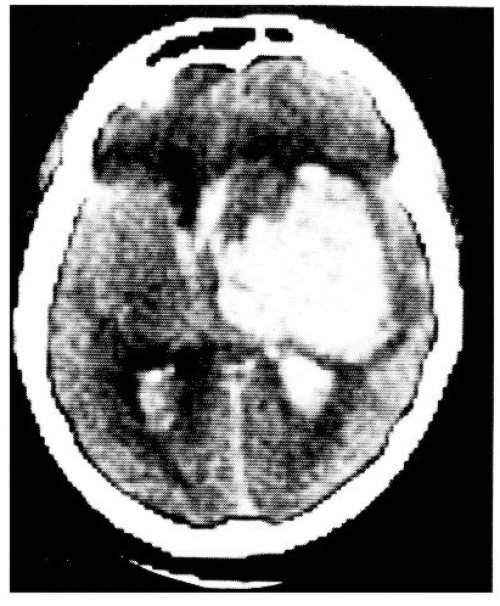

Komjuterizovana tomografija mozga:

Masivna hemoragija u predelu bazalnih ganglija (desno) sa krvarenjem u obe lateralne moždane komore.